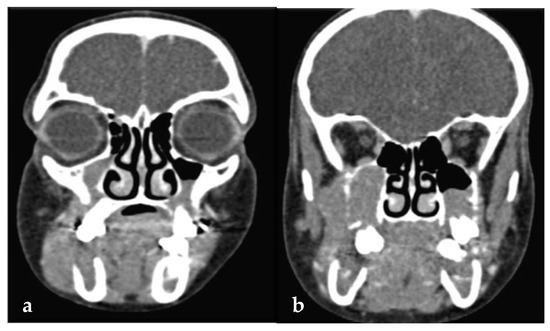

| 44 | Papadopoulou et al., 2024 (present case) | 11 | F | Painful swellings of the gingiva of the lower molars, tooth hypermobility, and facial asymmetry | Bilateral gingival swellings (erythematous and focally ulcerated) adjacent to mandibular premolars and molars that were hypermobile, displaced, and partially extruded Facial swelling along the right posterior mandible | Panoramic radiograph: ill-defined radiolucencies in the posterior mandible bilaterally, ‘floating-in-air’ teeth appearance CT: hypodense masses along and distal to the mandibular ramus extending upwards into the maxillary sinuses bilaterally, and the posterior wall of the right orbit; perforation of the right mandibular cortex | 11 years, no recurrence |